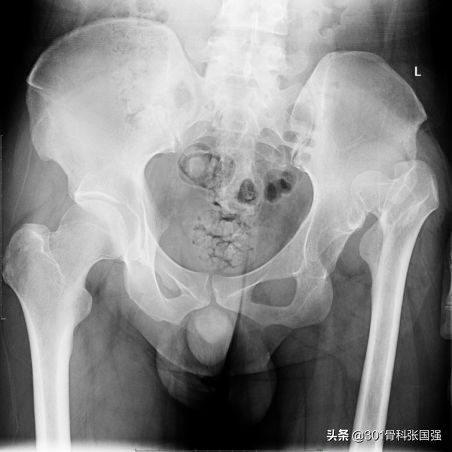

发育性髋关节发育不良合并髋关节脱位

大家也习惯叫“先髋”,当合并髋关节脱位时,患肢会出现严重的短缩,软组织也存在挛缩,如果将其下拉到应有的长度,很有可能会出现神经、肌肉、血管的牵拉损伤,部分可能还需要做短缩截骨,这也是在髋关节置换中难度系数较大的病例。

髋关节脱位 + 既往髋关节手术史

在髋关节脱位的病友中,若以前有过髋关节手术史,如多次保髋手术史,感染清创史,外伤后内固定史等等,都有可能影响肢体长短的平衡。